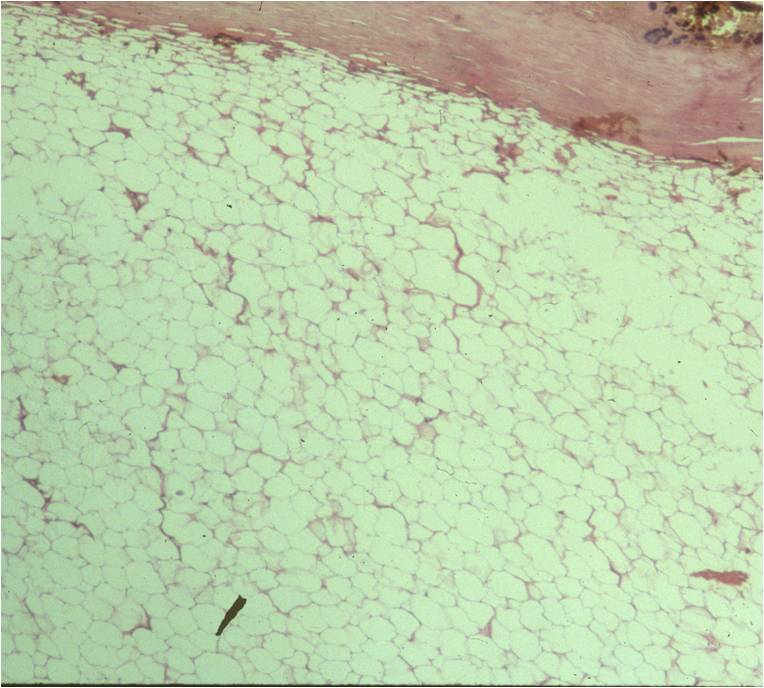

Fig. 4 & 5: Microscopic Pathology of a lipoma shows a homogeneous structure in low and high magnification with a uniform cell pattern and peripheral compressed nuclei barely discernible. Mature adipocytes. No mitoses.